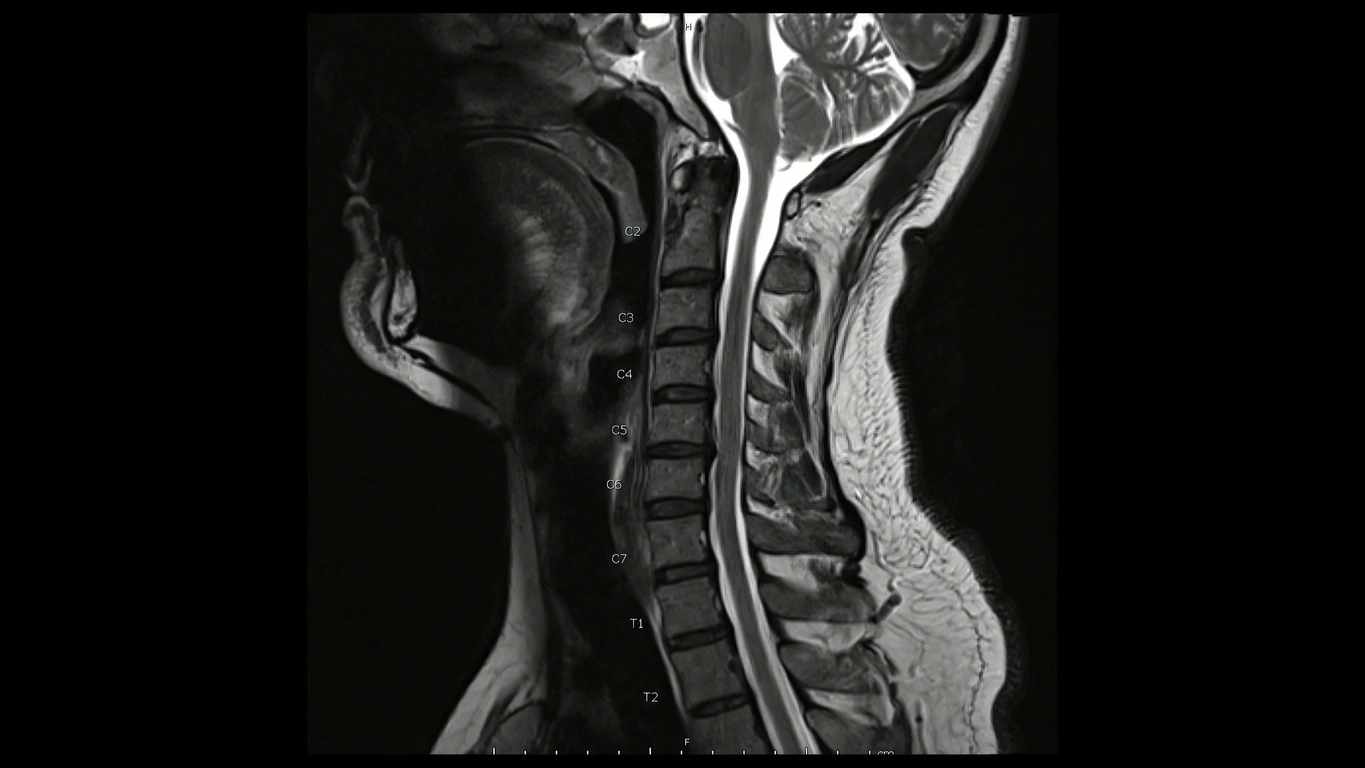

Common Diagnostic Techniques to Identify a Bulging Disc

Diagnosing a bulging C5-C6 disc usually begins with an in-depth physical exam and a review of the patient’s medical history. Physicians will ask about the nature and duration of the pain and any activities that may worsen the symptoms. Following this, various imaging tests such as X-rays, MRI scans, and CT scans become crucial in accurately diagnosing a bulging disc. While an X-ray can provide a clear image of the bones and rule out other conditions causing similar symptoms, it cannot visualize soft tissues like discs, necessitating MRI scans.

MRI scans provide a detailed image of both bones and soft tissues, allowing doctors to identify any disc abnormalities and measure the size of the bulge. A CT scan may be employed in some situations to get a more detailed 3D spine image. Further confirmation of the diagnosis can be achieved through nerve function tests if necessary. These combined methods ensure a precise diagnosis, essential for effective treatment planning.